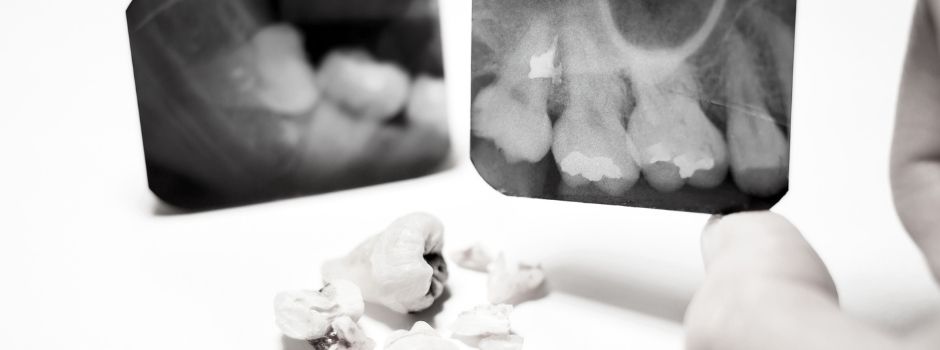

Radiografías Intraorales

Radiografías periapicales, técnica bite-wing y oclusales con alta definición digital.